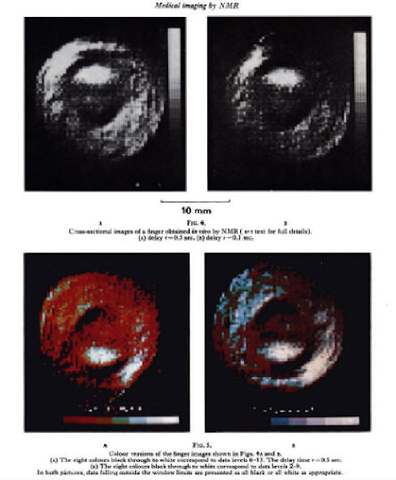

• RESONANCIA MAGNÉTICA: Primera imagen

RESONANCIA MAGNÉTICA: Primera imagen

Mansfield y sus colegas de Inglaterra publican la primera imagen de un dedo humano obtenida por resonancia magnética.